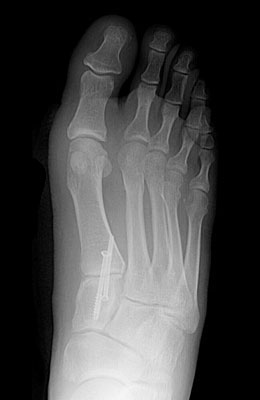

Before

Lapidus Forever Bunionectomy™ Before image

After

Lapidus Forever Bunionectomy™ after image

Lapidus Forever Bunionectomy™

Whitney, a 47-year-old businesswoman who could not fit into her dress shoes because of her bunion and terrible calluses caused by it. We performed a Lapidus Forever Bunionectomy™ on her big toes and she was able to bear weight on her foot 2 weeks after surgery and was back in her heels at 8 weeks post-surgery with no pain and now an amazing looking foot. After image was taken 12 weeks post-op.